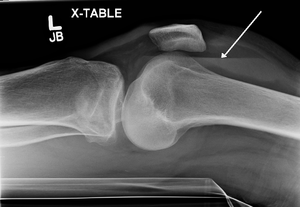

| Lipohemarthrosis (blood and fat in the joint space) seen in a person with a subtle tibial plateau fracture. The arrow indicates a fluid level between the upper fat component and the lower blood component. | |